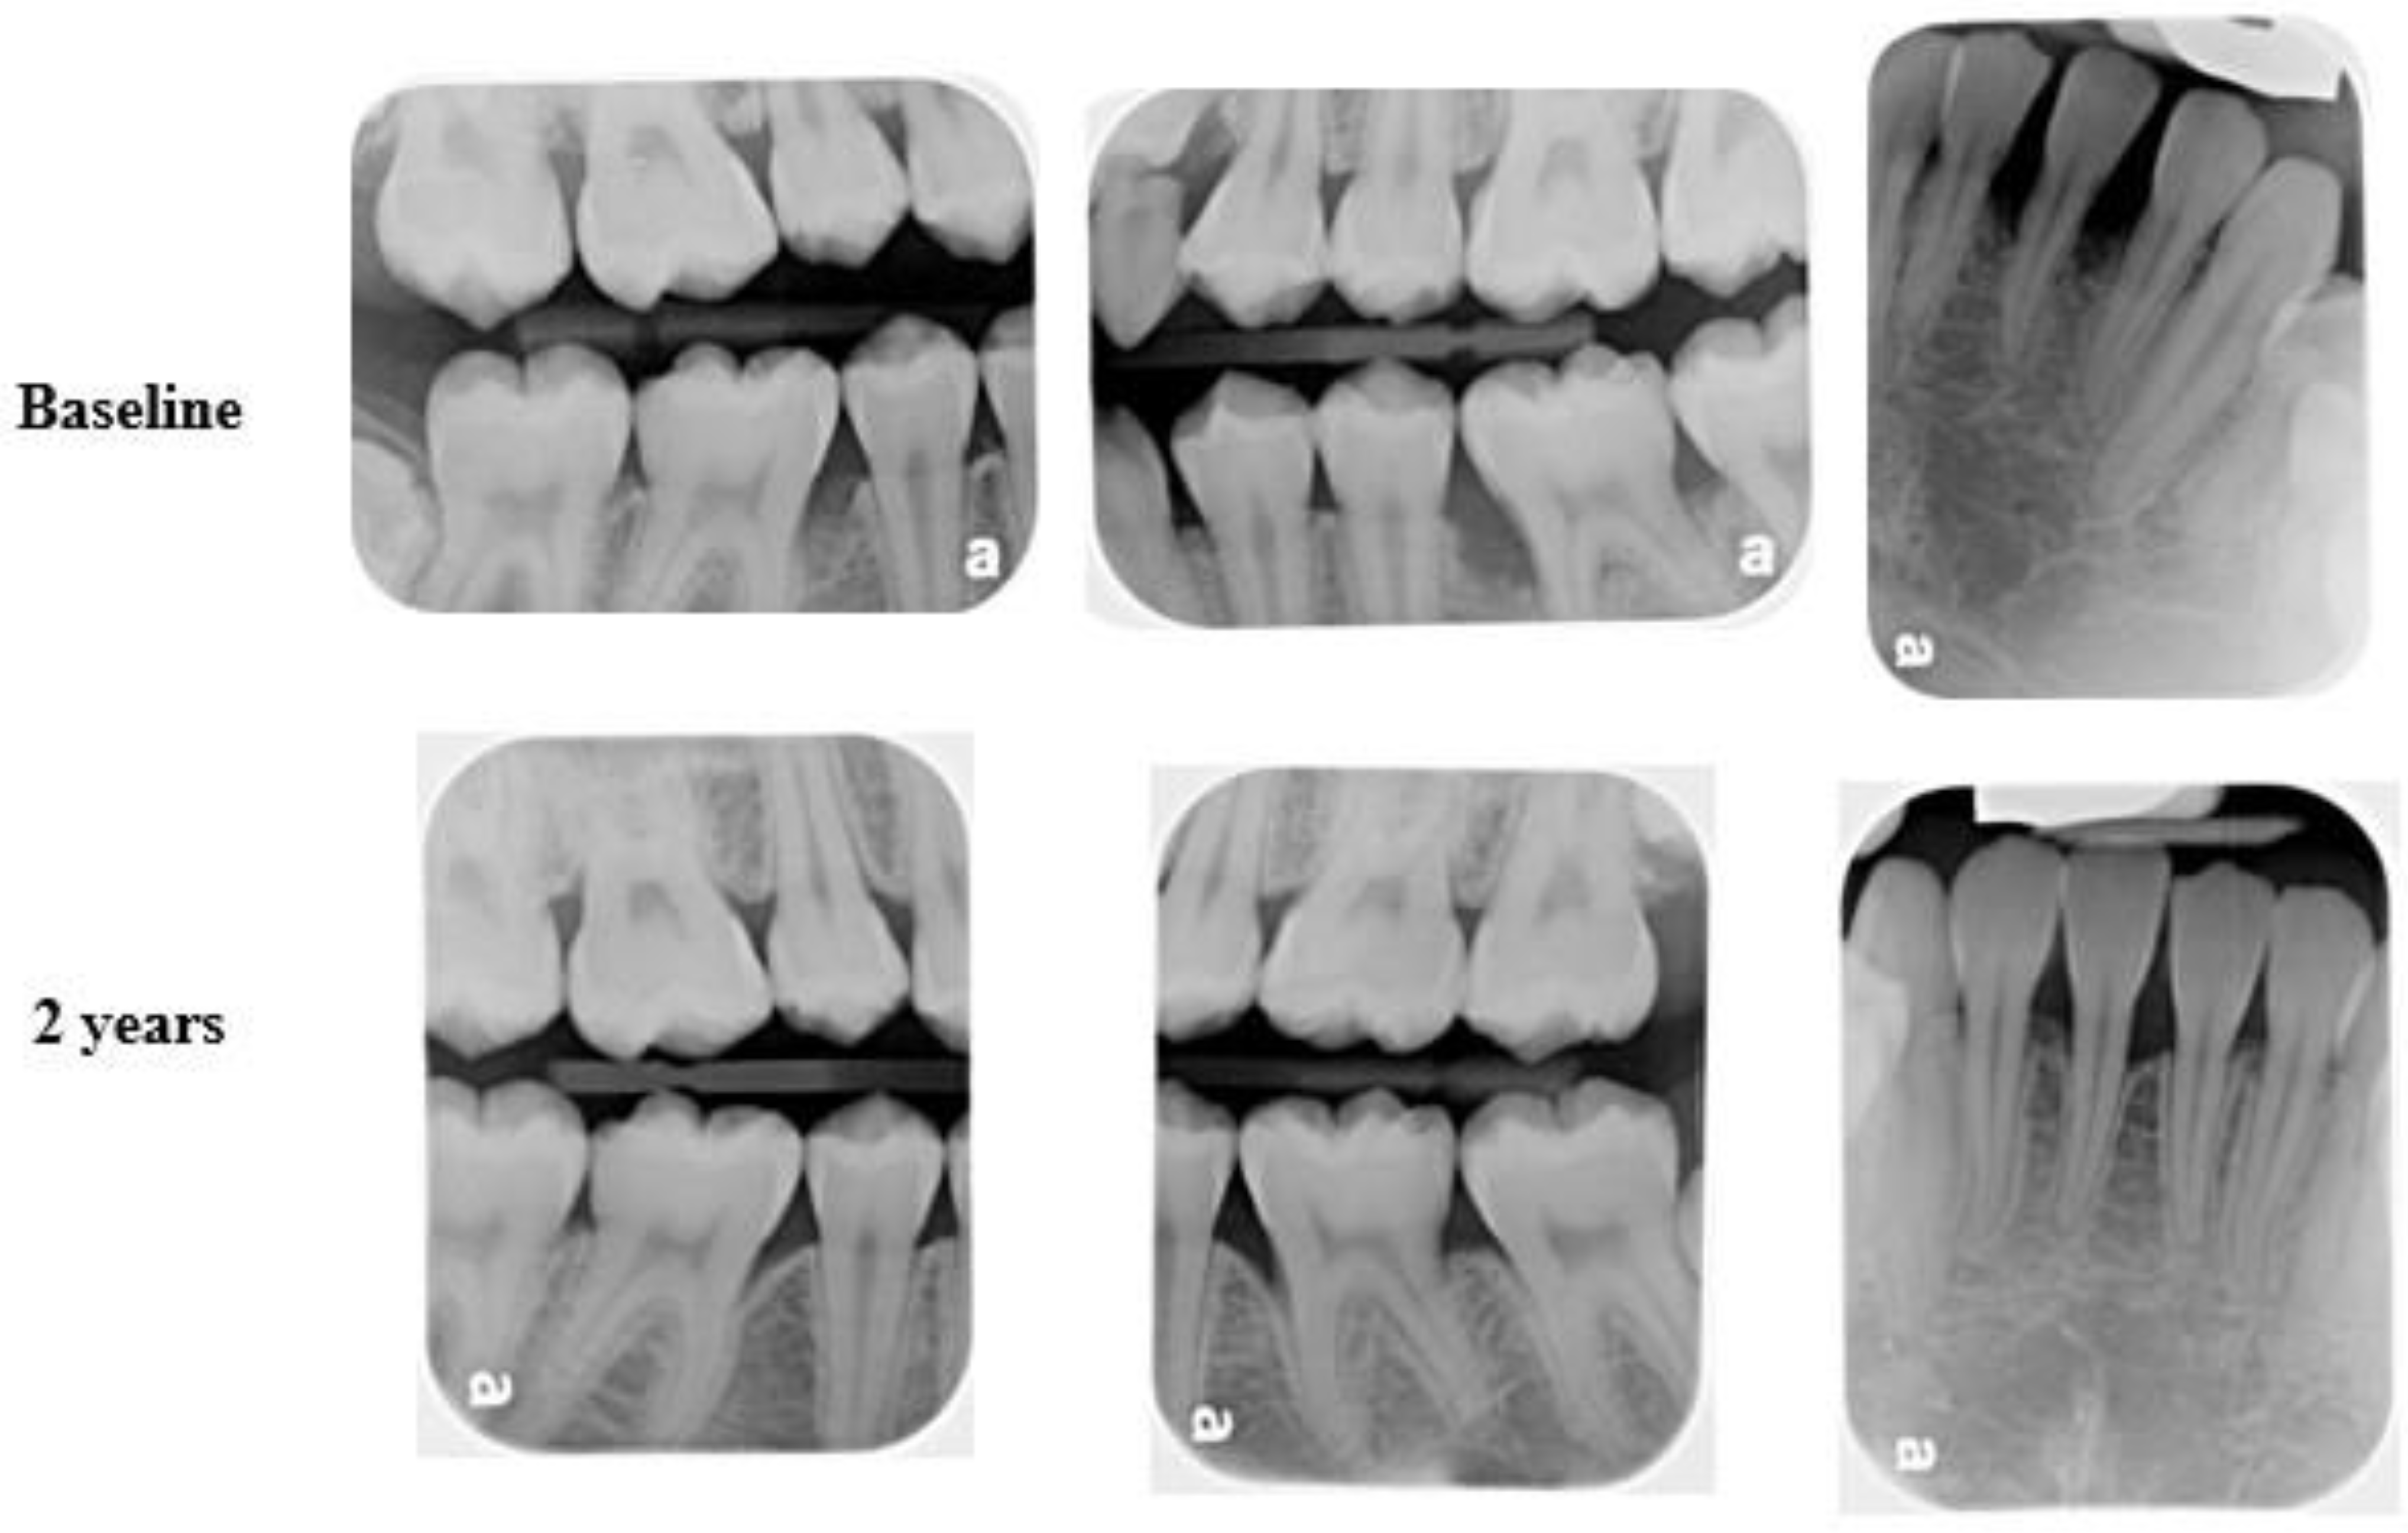

Figure 8.

Female patient diagnosed with C-MIP presenting bone loss in the incisors (25) and 1st permanent molars (baseline-upper). After SRP + ABX treatment, bone fill and stability were achieved at 2 years of follow-up (bottom).